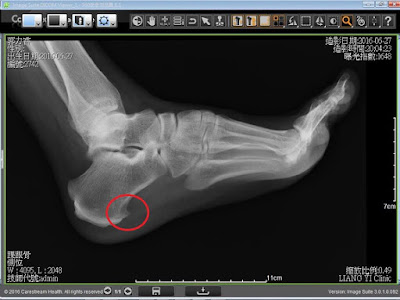

蹠骨頭位於腳底前部,腳趾與腳掌相接之突起處。由於在走路過程中,身體重量在單腳站立期時由蹠骨頭及腳跟各負擔一半,而在站立末期時全身的重量都壓在腳的蹠骨頭上,甚至在跑步時,第一和第二蹠骨頭受到地面衝擊力可高達體重的3倍,而每個人一天光是走路就要走一萬步左右,可以知道足部的負擔有多麼大,因此任何下肢或足部力學的不平衡,都容易有蹠痛的問題。

造成蹠骨疼痛的主要原因是該部位承受的壓力過大。從過往經驗來看,可綜歸以下幾種因素。

1、過度使用損害或受壓,如從事足部高衝擊性的運動,如跑步或彈跳運動者。2、穿著不適當的鞋子,如穿高跟鞋或鞋子楦頭過窄且堅硬的鞋子行走也會有蹠痛;或是長期穿不合腳型的鞋子, 如高足弓者穿足弓支撐不夠的鞋子的人,也是蹠痛好發族群。

4、腳底長雞眼、姆趾外翻或腳趾頭變形、腳跟肌腱過緊、或因年紀增長脂肪墊變薄或退化等。

5、足弓偏低或偏高